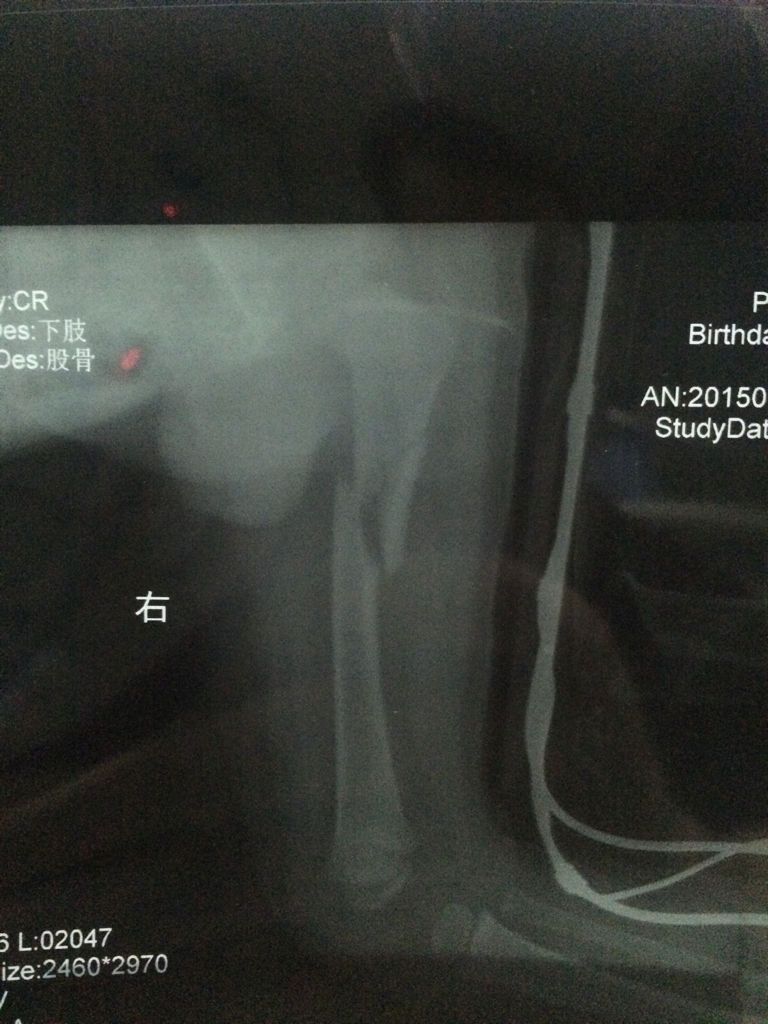

有骨科医生吗?求求你帮帮我,我儿子才一岁零九个月,于7月27日下午玩耍把右大腿骨折了,有点严重,现在在县城中医院就诊,医生叫我们保守治疗,但是我不懂,我看片子恢复得不怎么样,我怕儿子以后会有后遗症,现在好难过,求求你们救救我儿子,帮我给点建议!